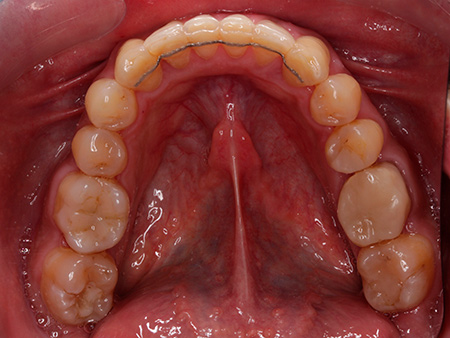

José ya había finalizado un tratamiento de ortodoncia con brackets metálicos antes de acudir a Ferrus & Bratos. Sin embargo, no había utilizado retenedores, por lo que los dientes habían vuelto a moverse con el paso de los años. Por ello, tenía mucho interés en conseguir una sonrisa alineada y funcional.

Por su trabajo, José viaja mucho y en ocasiones pasa más de un mes fuera de casa, por lo que la doctora Patricia Bratos le recomendó la ortodoncia con Invisalign, pues las revisiones en este caso son cada 4 o 6 semanas. Después de una ortodoncia de 24 meses de duración, nuestro paciente está encantado con el resultado y también con el trato recibido.